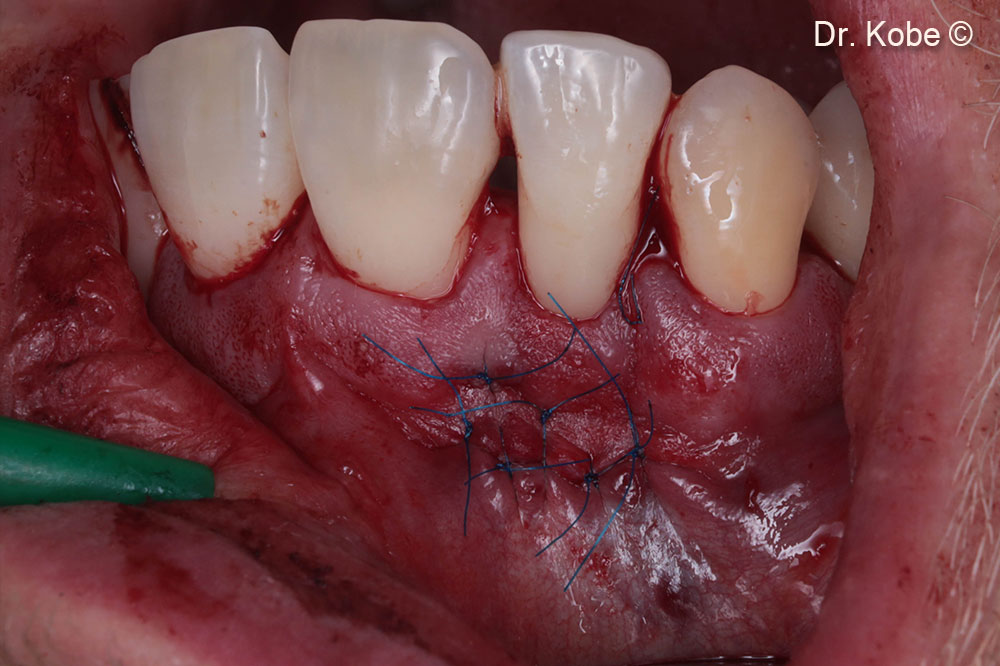

Rạch ngang (NIPSA) ở tiền đình

Truy cập vào lỗi

Khuyết tật được lấp đầy bằng Gen-OS

Vết thương được khâu bằng các mũi khâu gián đoạn